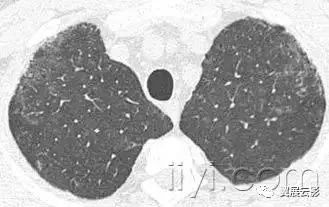

二十、铺路石征:

CT扫描:铺路石征表现为磨玻璃影背景上小叶间隔和小叶内线增厚,呈现不规则的铺路石征。铺路石征常与相对正常肺组织分界清楚,边缘规则。该征象最早报道于肺泡蛋白沉积症,也可见于其他类型同时累及肺间质和肺实质的弥漫性肺疾病,包括脂性肺炎。